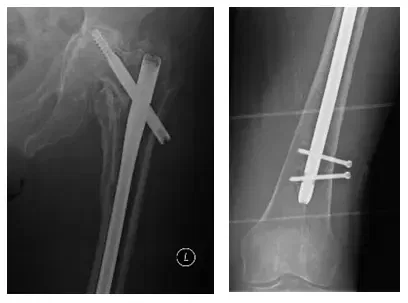

La paciente es una mujer de 75 años que acudió a nosotros con dolor intenso en la cadera izquierda tras someterse a una fijación interna de reducción abierta (ORIF) de la cadera izquierda. El paciente vino con radiografías para revisar, como se muestra a continuación, y las radiografías indican que el hardware había fallado.

Las radiografías muestran una fijación interna por reducción abierta de una fractura intertrocantérica de cadera izquierda.

Las radiografías muestran cambios osteolíticos extensos en el fémur proximal, así como osteoartritis avanzada en la cadera izquierda.